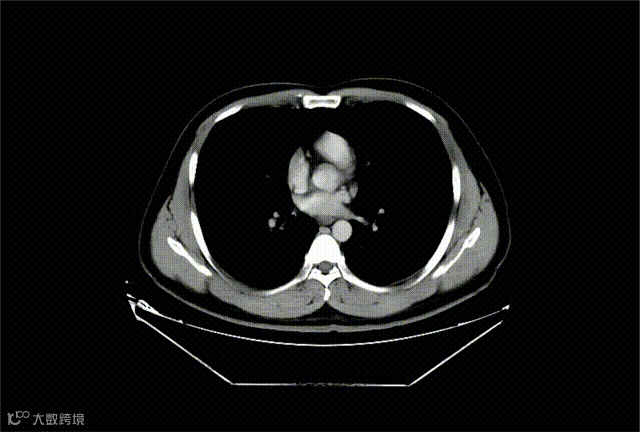

术前影像学检查(术前评估)

CT肺部+门脉造影示

1.双肺多发小结节,考虑炎性结节可能,随诊。

2.右肺中叶及左肺上叶,双肺下叶少许炎症,部分为慢性或陈旧性炎症。

3.肝硬化。

4.脾大伴多发梗死灶可能。

5.右肝占位,考虑介入术后改变。

6.肝内多发囊肿可能。

7.右肝膈下钙化灶。

8.胆囊结石。

9.食管下段、胃底及脾门多发增粗迂曲血管,考虑门脉高压可能。

10.门静脉主干及其左支血栓形成。